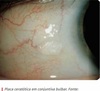

caracteristcas da sd sturge weber

mancha em vinho do porto(hemangioma facial) + hemangioma neptomeningeos + angioma episclerais (glaucoma pos trabecular)